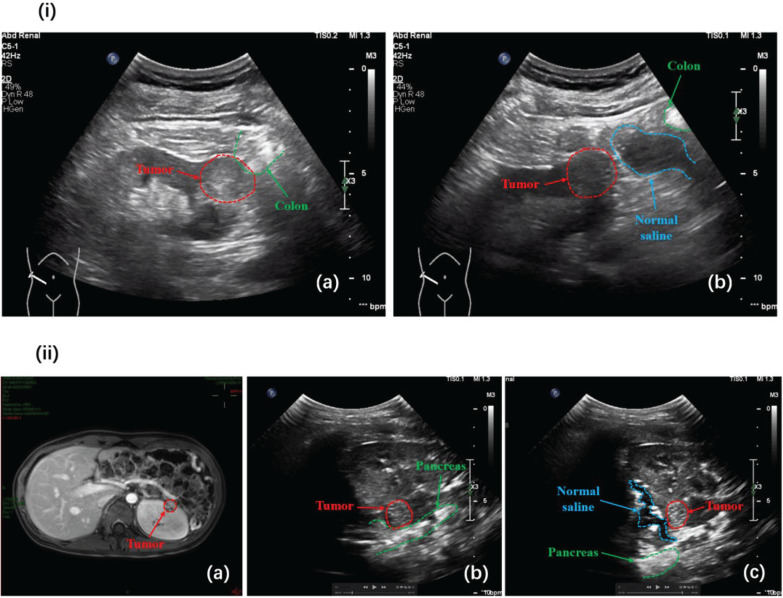

Purpose: To evaluate the trifecta outcomes of ultrasound-guided radiofrequency ablation (RFA) of T1a renal masses and to identify factors influencing trifecta outcomes.

Materials and methods: We retrospectively reviewed data from patients who underwent ultrasound-guided RFA at Peking University First Hospital between March 2017 and May 2024. Baseline demographics, perioperative outcomes and follow-up results were collected. The trifecta outcomes were defined as the absence of severe complications, incomplete ablation and tumour recurrence. Multivariate logistic regression analysis was performed to identify risk factors for trifecta failure.